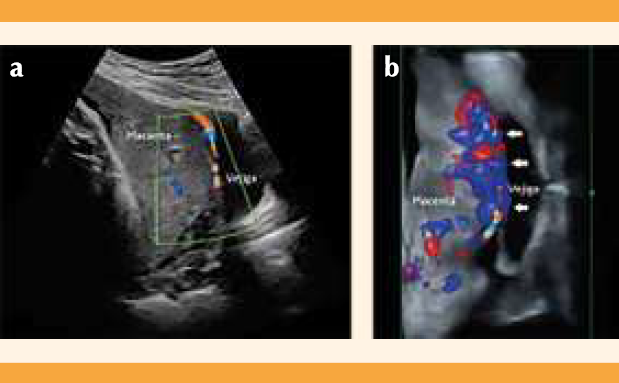

Paciente de 20 años, con antecedente de 3 embarazos y 2 cesáreas; sin procedimientos quirúrgicos y con un embarazo gemelar bicorial biamniótico atendida en el Departamento de Medicina Fetal e Imagenología del Hospital de Ginecoobstetricia del Centro Médico Nacional de Occidente. En la valoración ultrasonográfica (equipo GE Voluson E6 y transductor convexo 3.5 Hz) efectuada a las 36 semanas se detectaron dos fetos vivos y dos placentas, una en el fondo uterino y la otra con inserción en el cuerpo uterino, en su cara anterior e inferior, con sospecha de inserción marginal al orificio cervical interno. Se descartó el diagnóstico de placenta previa por vía vaginal, mediante el transductor endocavitario de 7.5 Hz, con borde inferior placentario a más de 30 mm del orificio cervical interno (Figura 1a). Se detectaron signos ecográficos de acretismo placentario. En la revisión trans-abdominal se advirtieron: pérdida de la línea hipoecoica, adelgazamiento del miometrio, abombamiento hacia la vejiga, interrupción de la pared vesical (Figura 1b) e hipervascularidad útero-vesical (Figura 2a). Por vía transvaginal: hipervascularidad subplacentaria e hipervascularidad útero-vesical con Doppler 3D (Figura 2b). No se observaron lagunas placentarias, vasos alimentadores de lagunas ni hipervascularidad intraplacentaria.

Figura 2 Ultrasonido transabdominal. (a) Modo duplex, se observa hipervascularidad útero-vesical. (b) 3D + Doppler color, que muestra hipervascularidad subplacentaria y útero-vesical, con vasos que cruzan la interfase (flechas).